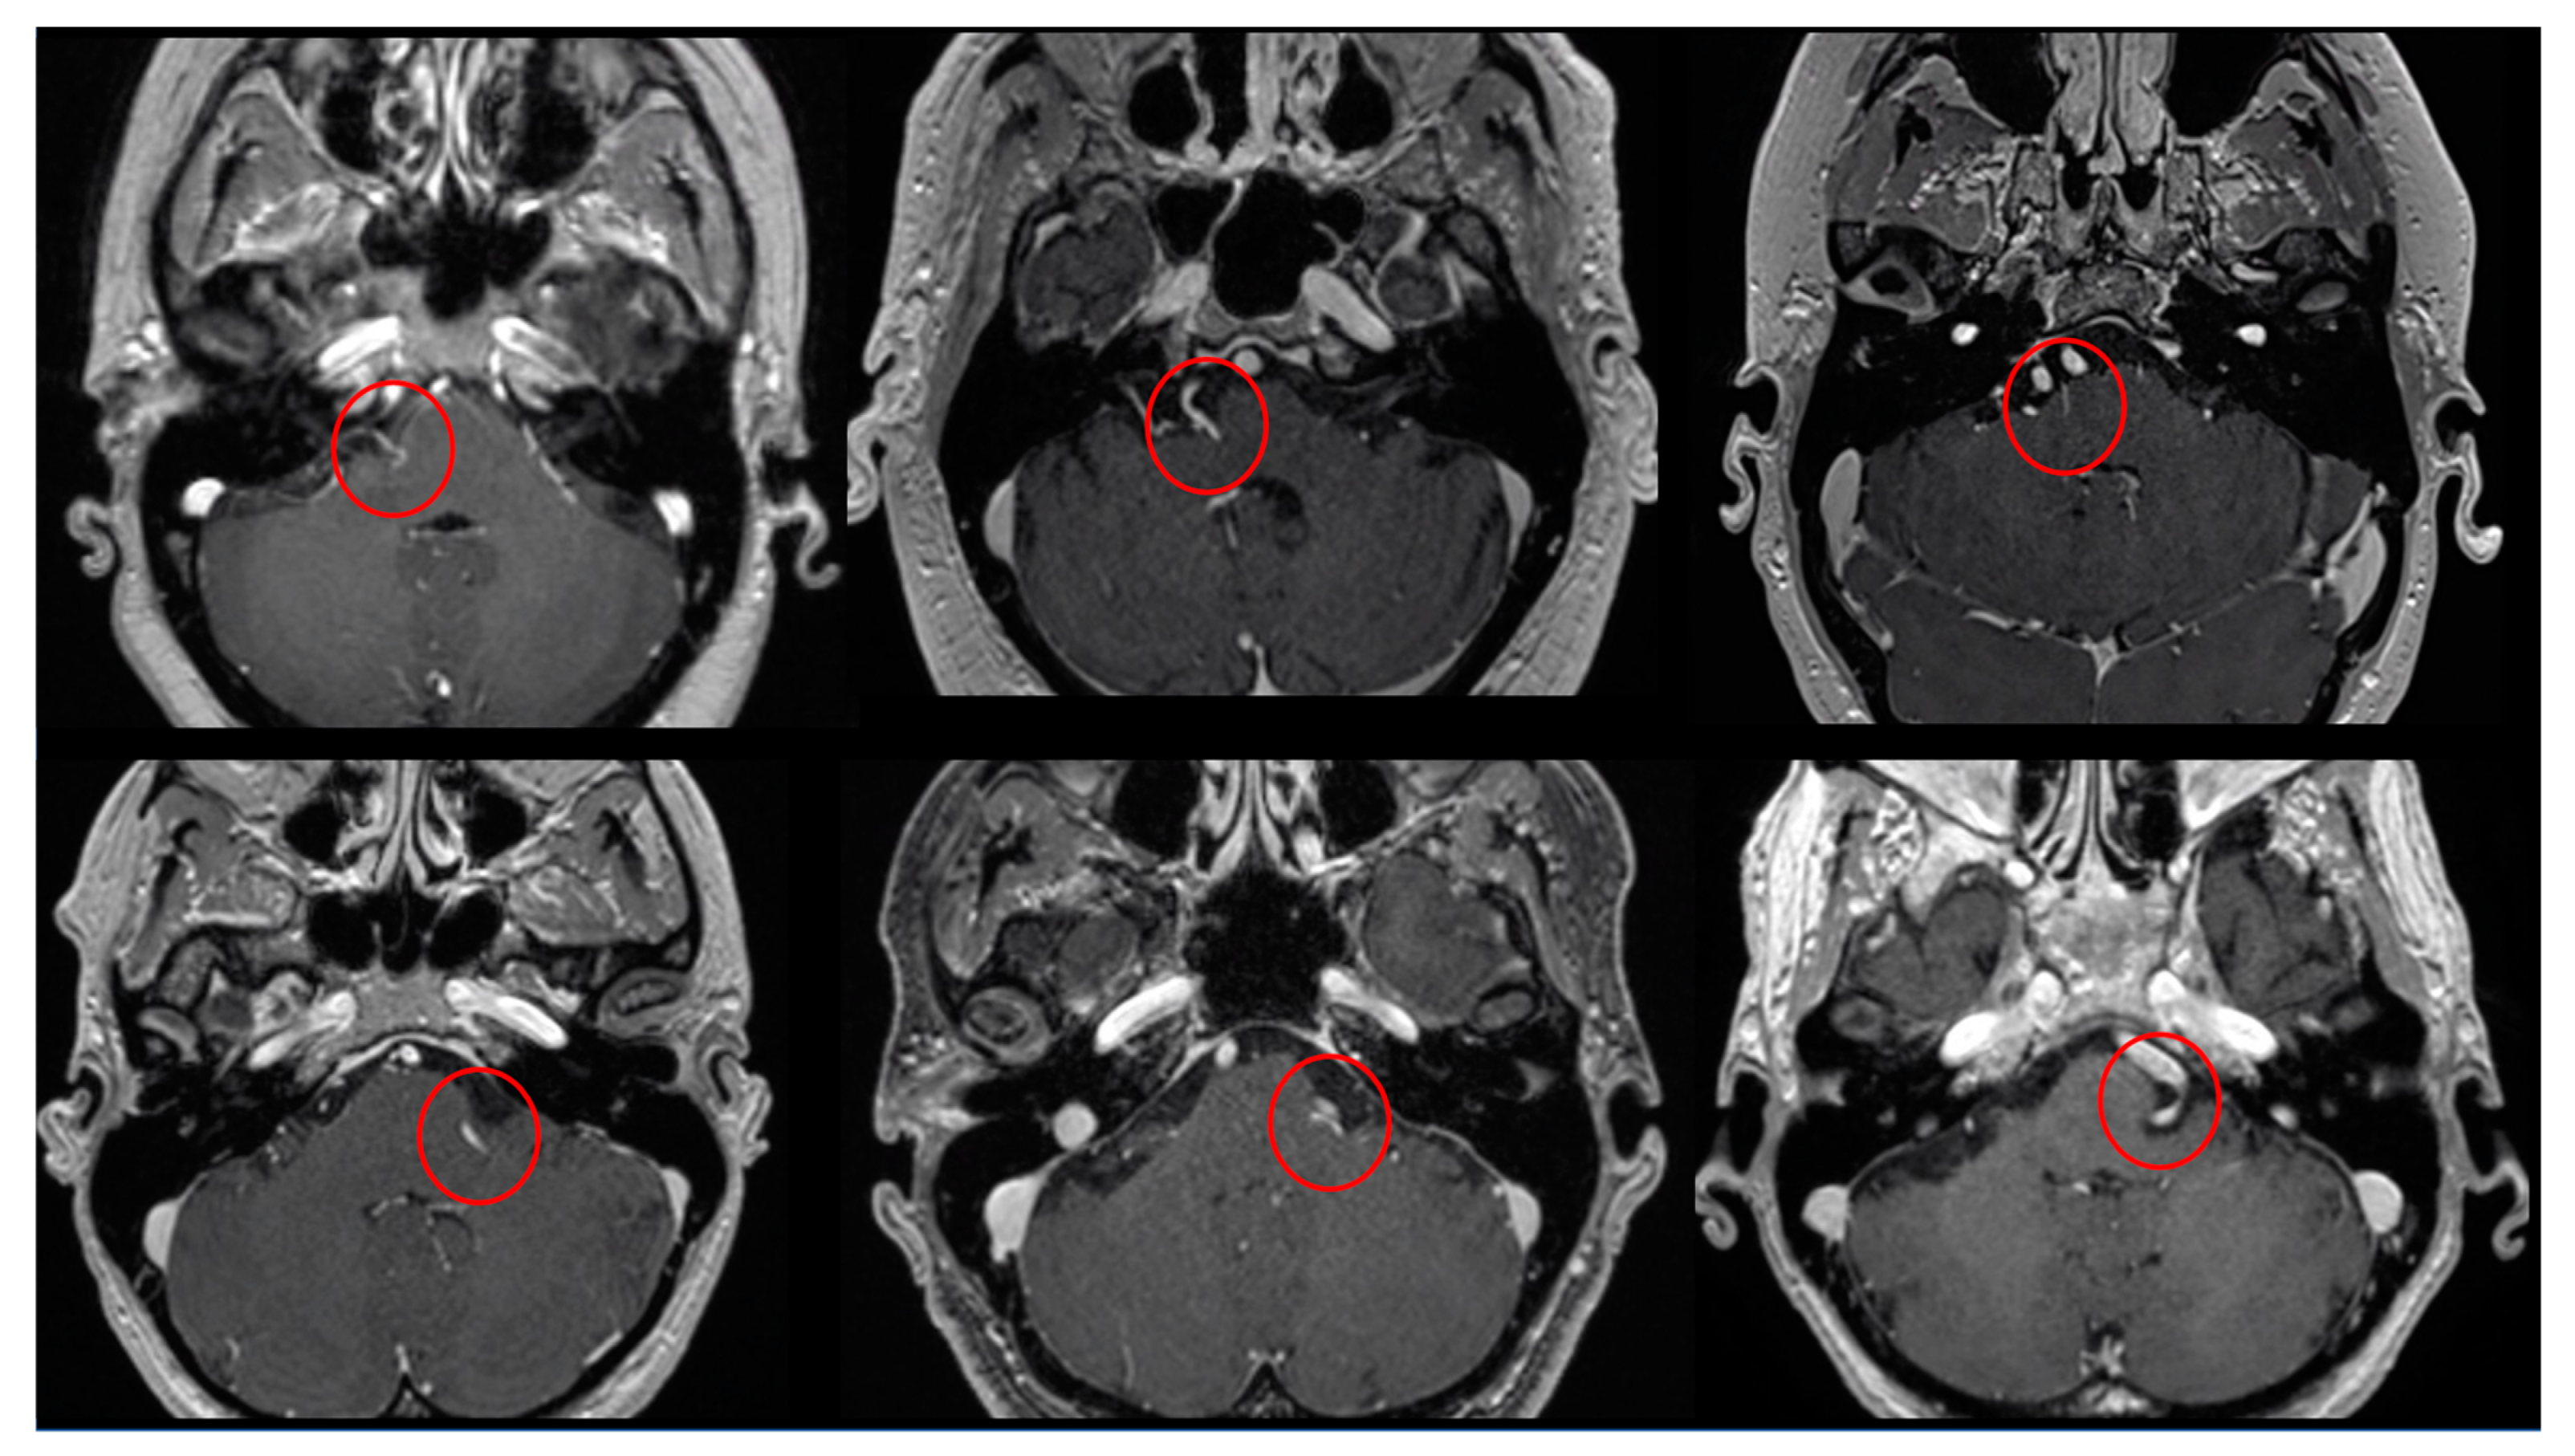

Figure 2.

Six examples of the PS identified (inside the red circles) in T1WI with gadolinium axial images.